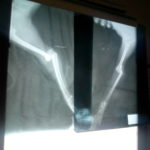

Por nuestros hermanos sin voz A.C. Recibi una llamada de ayuda por una vecina reportando que habian atropellado a un perrito cerca de donde me encontraba, fui de inmediato, lo tome y me dirigí al veterinario, se le dio toda la intervención, logrando su recuperación. Agradeciendo a todos los que me apoyaron, dios los bendiga!!!… Aqui demuestro totalmente mi labor, sigan apoyando por nuestros hermanos sin voz. YOLANDA ROMERO NUÑEZ » IMG_20181002_170941